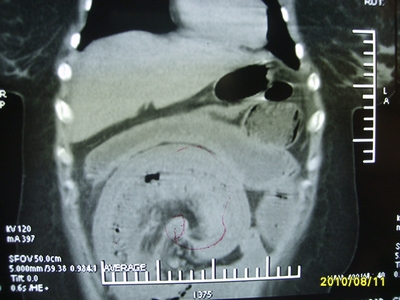

5天前突发腹痛剧烈难忍,伴解淡血水样便。近一天来腹痛缓解,没有明显的腹膜炎的体征。今天照的腹部ct。从ct上看感觉是一个绞窄性肠梗阻,但是现在没有腹痛。不好解释

要有麻烦了,感觉小肠有套叠还有扭转改变,估计部分已有坏死。

高位肠梗阻(不全性),原因小肠(空肠)扭转,肠壁水肿增厚,成年人肠梗阻要排除合并占位,建议手术。

绞窄性肠梗阻_肠管套叠 扭转,肠壁明显水肿。

支持绞窄性肠梗阻,肠壁明显水肿并见有多发小泡状积气--肠坏死

考虑绞窄性肠梗阻并肠坏死。